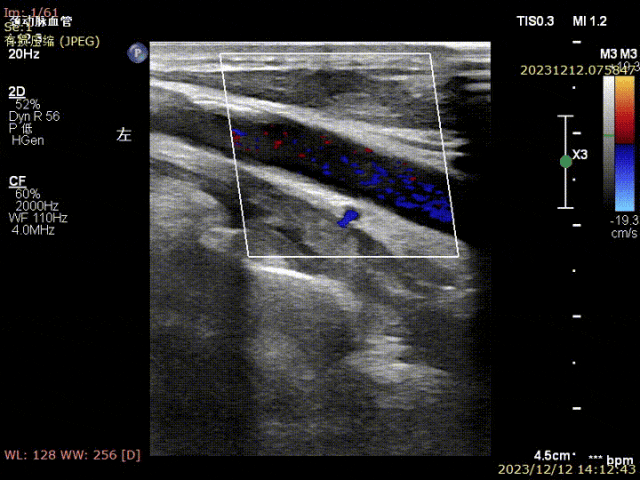

姜坤主任接診后做彩超發(fā)現(xiàn)患者左側(cè)頸總動脈分叉處硬化斑塊鈣化嚴(yán)重,頸內(nèi)動脈起始部重度狹窄(狹窄程度>90%),且斑塊為易損斑塊。

▲患者術(shù)前頸部血管超聲可見頸動脈斑塊,狹窄局部血流速度明顯減慢